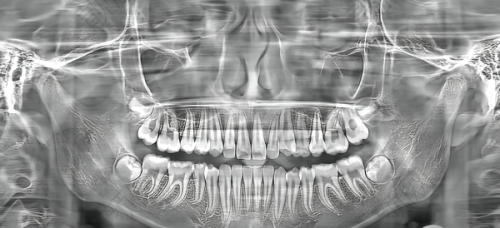

该门诊部的开诊项目丰富多样,能够满足不同患者的口腔需求。其中包括种植牙项目,对于那些缺失牙齿的患者来说,种植牙可以修复牙齿的功能和美观;正畸项目,能帮助改善牙列不规则、咬合不当、龅牙、突嘴等问题,让患者拥有整齐美观的牙齿;牙周治疗项目,可有效治疗牙周疾病,维护口腔健康;牙齿修复项目,能修复受损的牙齿,修复其正常的形态和功能;全口、半口假牙修复项目,为牙齿缺失较多的患者提供了合适的解决方案;牙冠治疗补救项目,针对牙冠出现问题的情况进行修复;洗牙项目,则可以清洁牙齿,预防口腔疾病。